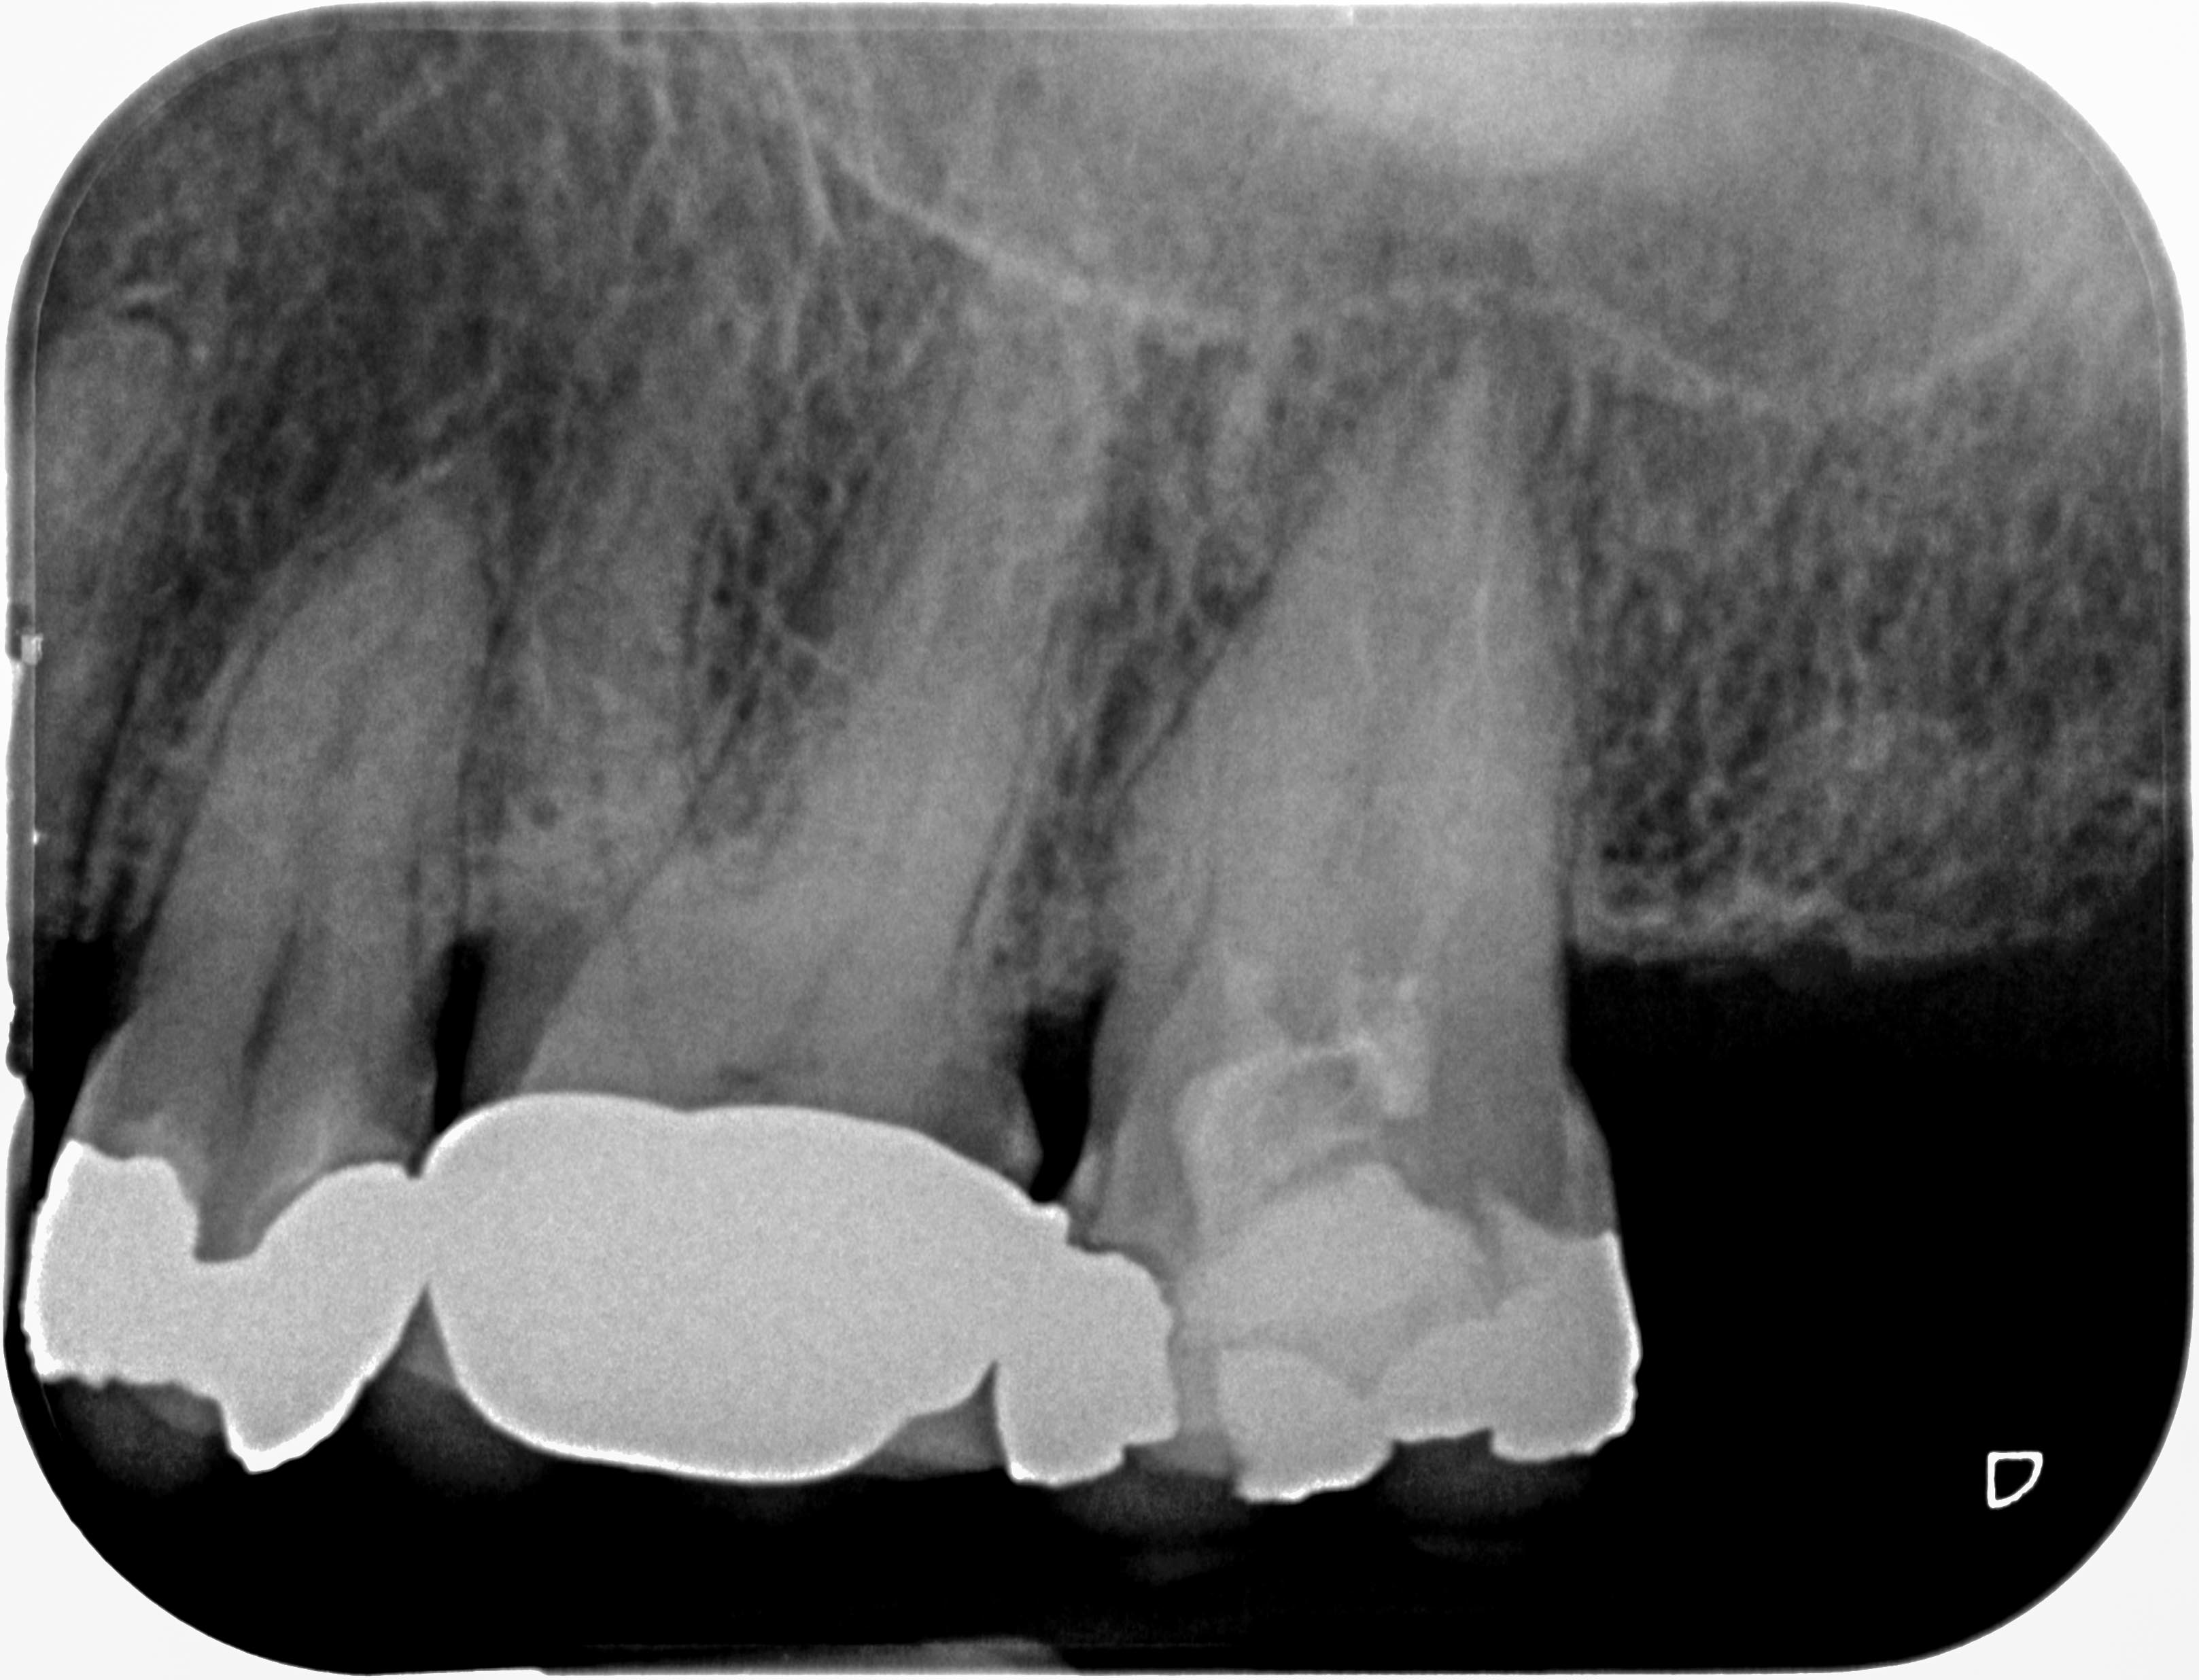

KC27-1 Veröffentlicht 26. Mai 2014 am 3235 × 2472 in Geht´s auch ohne DVT ? Zahn 27 – diagnostische Rö